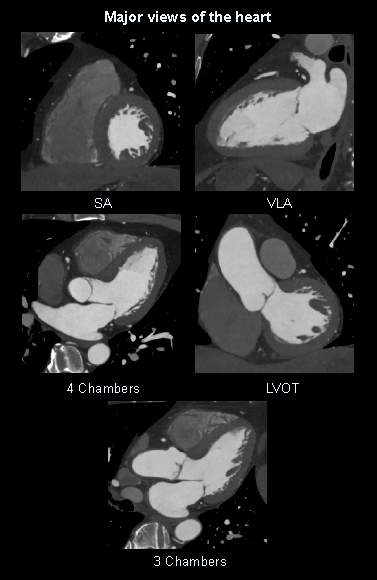

- 2D views of the heart or multiplanar reformations (MPRs): four chambers, three chambers, left ventricular outflow track (LVOT), short axis (SA) and vertical long axis (VLA).